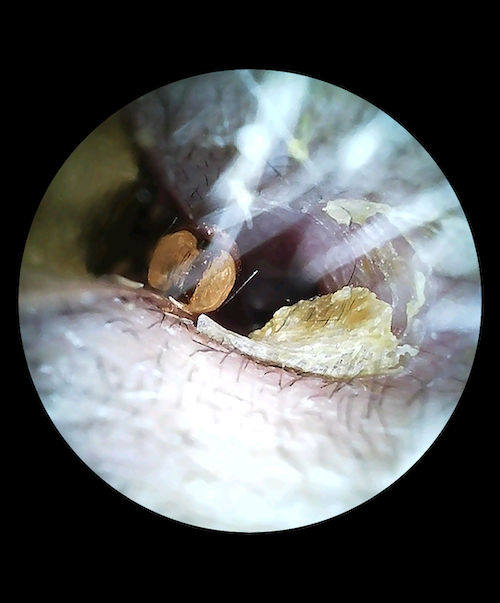

耳内部の4K映像スクリーンショット、使った本人の耳の中が汚ぎてびっくりしました!(閲覧注意)

今まで生きてきて自分の耳の中を見る機会ってそうそうないと思うんですが、結構衝撃的です!!

4K解像度のカメラは本当に鮮明で、耳垢の色や質感まではっきり分かります。「こんなところに耳垢があったのか!」という発見が何度もありました。